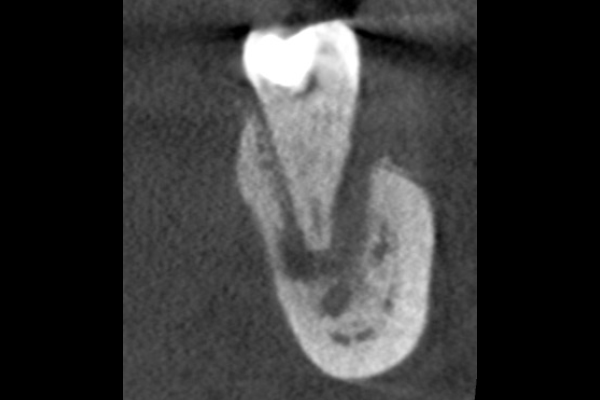

40代男性の大臼歯(奥歯)の症例

- 主訴

- 「時々歯茎が腫れる」とのことでご来院されました。数週間前から症状があり、他の医院では「抜歯の可能性がある」と言われ、不安に感じていらっしゃいました。

- 期間

- 治療期間2ヶ月、治療回数3回、レントゲン写真で治癒を確認できるまでの期間6ヶ月

- 治療内容

- 1.古い被せ物の除去と虫歯の徹底除去

まず、古い銀歯を外し、内部に広がっていた虫歯を丁寧に取り除きました。

2.マイクロスコープ下での根管治療

唾液などによる細菌の侵入を防ぐ「ラバーダム」を装着し、マイクロスコープ(歯科用顕微鏡)で根管内を数十倍に拡大しながら治療を進めました。複雑な形状の根管の内部まで、汚染された組織を徹底的に洗浄・消毒します。

3.根管充填(こんかんじゅうてん)

根管内が完全にクリーンになったことを確認し、再感染を防ぐために専用の薬剤で隙間なく密閉しました。

4.土台と被せ物の作製

歯の強度を補うための土台を立て、最終的なセラミックの被せ物を作製し、装着しました。

- 治療に伴うリスク

- 少しでも汚染物質が残ると再発のリスクが高まります。